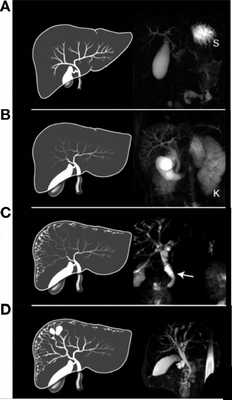

Рисунок 8 | МРХПГ и последующий рендеринг билиарной системы с аномалиями, свойственными для пациентов с ПБП-АР:

A. Нормальная печень с увеличенным желчным пузырем, (S) желудок.

B. Увеличенный общий желчный проток с желчным пузырем. Расширенные внутрипеченочные протоки.

C. Веретенообразные кисты периферических и центральных желчных протоков небольшого размера с расширенным общим желчным протоком (стрелка) и желчным пузырем.

D. Веретенообразные макроцисты с расширенными печеночными протоками.

У всех пациентов была печень аномальной формы с непропорционально увеличенной левой долей.